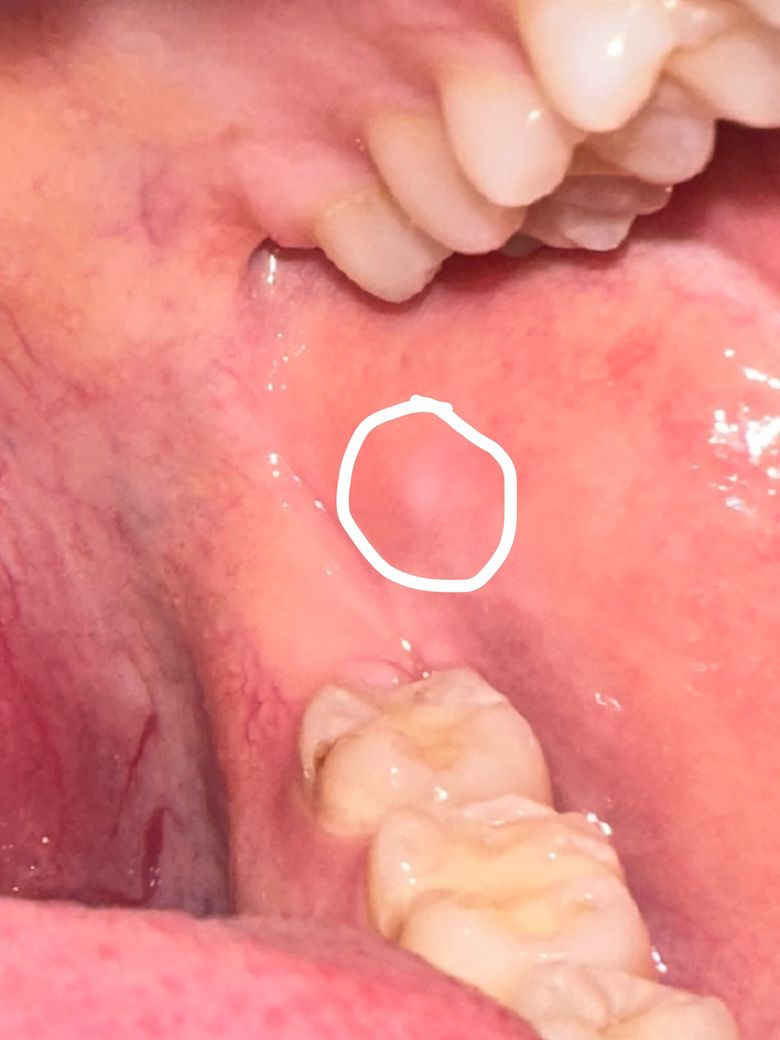

구내염 흔적인가요? 안좋은건 아닐지 걱정이에요

흰색 흉터? 흔적?이 남아있어요

저자리에 구내염 있었다가 없어졌는데

저렇게 흔적이 남아있어요

통증이나 이런건 없고

저 흰색 부분만 아주살짝 튀어나와있기도 해요

• 1번 째 사진

네 말 그대로 흔적같습니다 씹어서 생겼던 궤양이 없어진 흔적같고요 악성병소의 양상은 아닙니다

구내염이 치유된 자리에 하얀 흔적이 남은 것으로 보입니다.

사진에서 피막을 형성하는 것처럼 보이지 않으며, 두드러지게 융기되어 있거나 구진(papula)를 형성하지도 않은 것처럼 보입니다.

또한 궤양성 병소도 아니며 통증성 병소도 아닙니다.

따라서 구내염에서 갓 회복한 새로운 구강 점막 조직으로 추측합니다.

피부에 상처가 났다가 새 살이 돋으면 새로 돋은 살은 주변과 색이 살짝 다른 것을 연상하면 좋을 것 같습니다.

구강암과의 연관성은 떨어져보입니다.